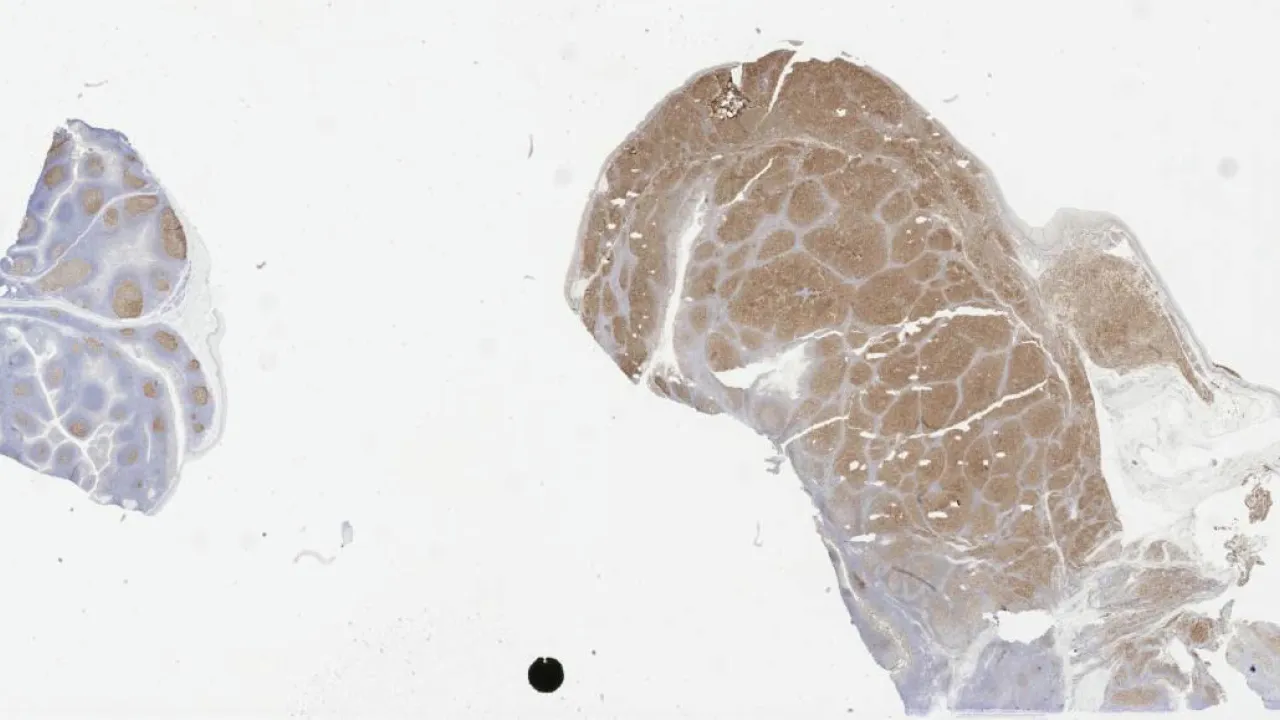

Lymph Nodes, Mantle cell lymphoma, CD5 stain